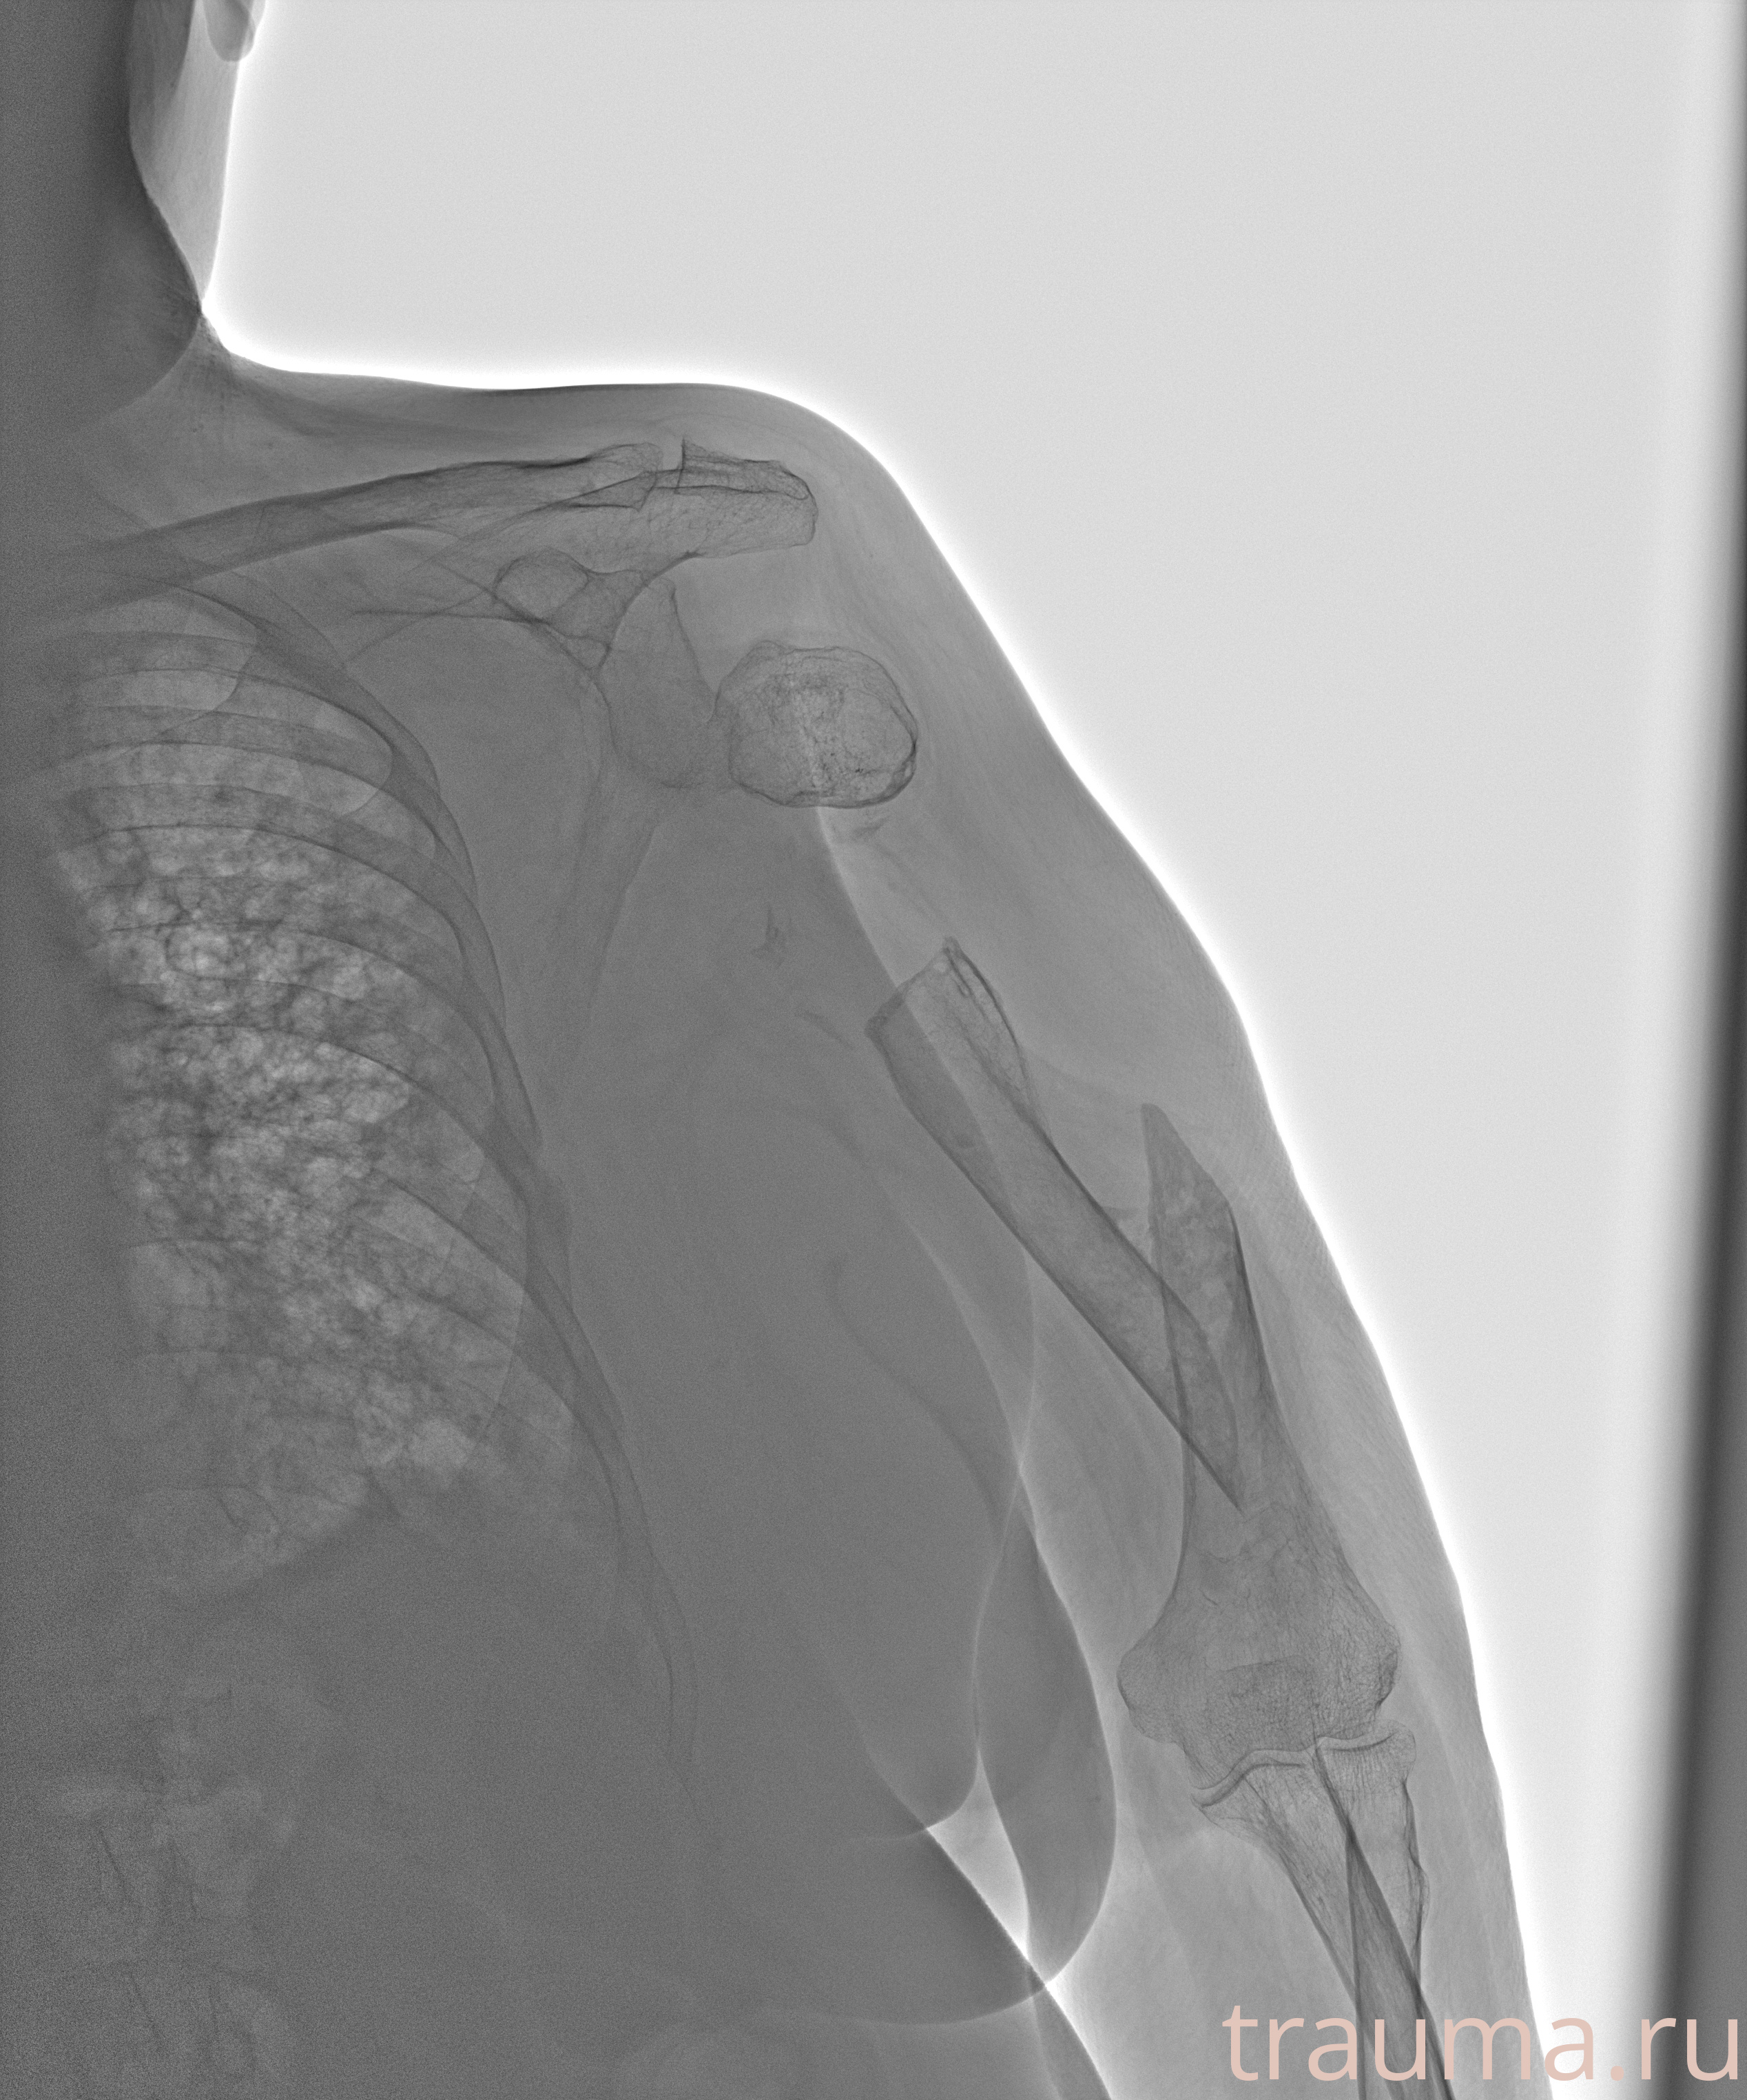

Рентгенограммы

Рентген на дому: по вашему адресу приезжает врач-рентгенолог, травматолог-ортопед с мобильным рентгеновским аппаратом, проводит диагностику травмы или заболевания, делает необходимые рентгенограммы, дает рекомендации по дальнейшему лечению. Получить качественные снимки в домашних условиях возможно благодаря уникальной методике, разработанной МосРентген Центром для института  Склифосовского

при переломе шейки бедра и пневмонии от компании МосРентген Центр - партнера Института имени Склифосовского